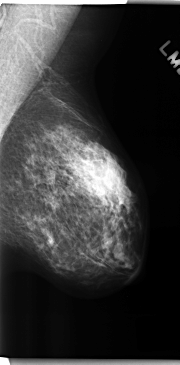

C_0222_1.LEFT_MLO

LEFT_MLO LINES 4736 PIXELS_PER_LINE 2328 BITS_PER_PIXEL 12 RESOLUTION 50 NON_OVERLAY